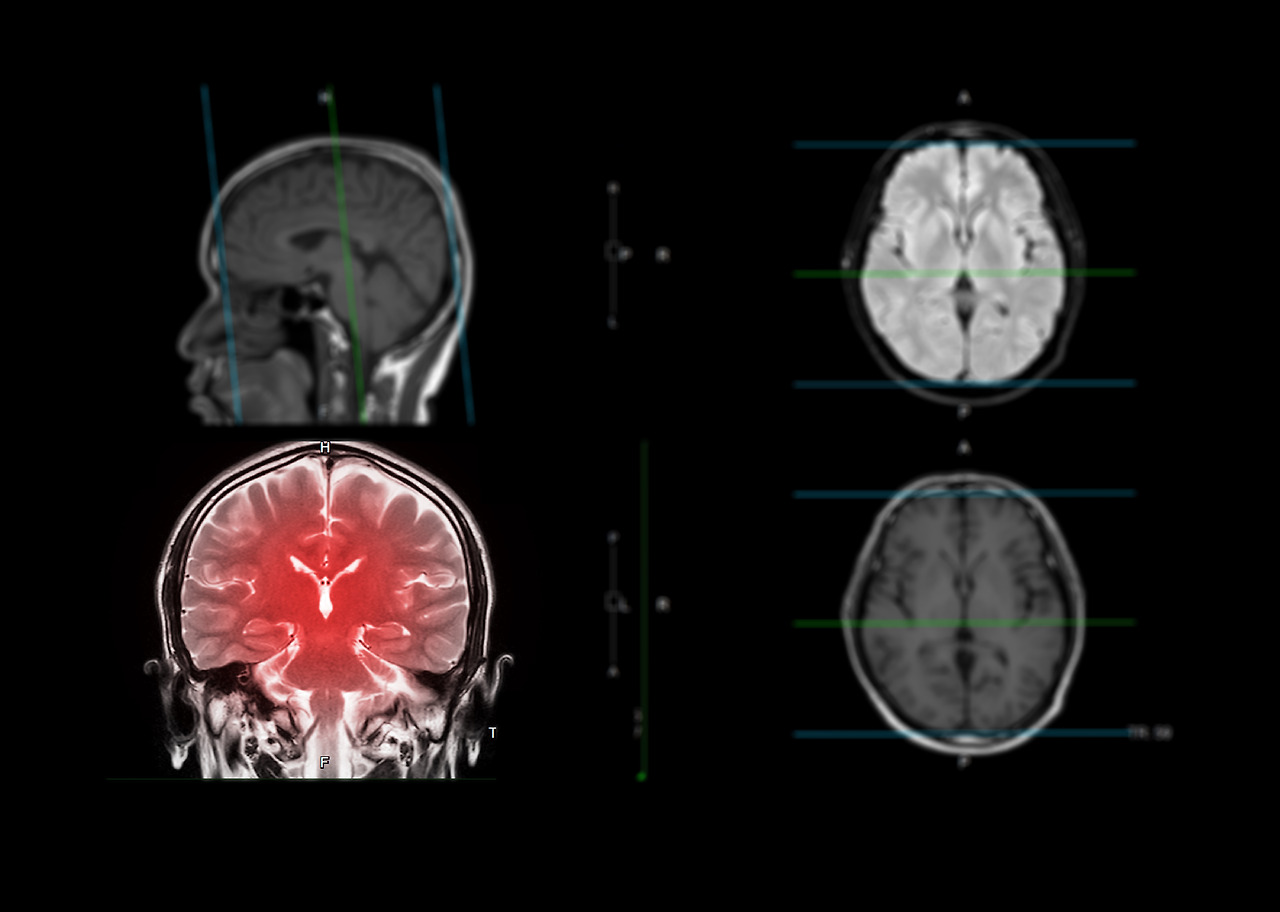

인제대학교 일산백병원 신경과 박혜리 교수팀은 노년 인구(평균나이 76세) 7천 959명을 대상으로 25년 추적 관찰한 결과를 내놨다. 연구팀은 1개월 동안 수면을 어떻게 취했는지 파악하고, 아밀로이드 PET 영상 검사를 통해 분석했다.

연구 결과 수면시간이 6시간 이하인 노인이, 7시간 이상 잠을 잔 노인에 비해 치매 발생 위험이 30%가량 증가했다.

수면장애 치료 전문의인 일산백병원 신경과 박혜리 교수는 “깊은 잠을 잘 때 뇌의 글림프 시스템(glymphatic system)이 활성화돼 신경독성물질을 청소한다”며 “수면이 부족하면 이 과정이 제대로 작용하지 않아 뇌 건강이 악화할 수 있다”고 말했다.

또 박혜리 교수는 “수면 시 우리 몸은 베타아밀로이드 등 신경독성물질을 해독하는데, 수면에 문제가 생기면 이러한 독성물질이 뇌에 침착돼 치매를 유발할 수 있다”고 설명했다.

'글림프 시스템‘은 뇌의 노폐물은 림프계를 통한 배출이 불가능하기 때문에, 척수액이 뇌로 유입되어 이를 씻어내는 프로세스를 통해서 제거되는 과정을 말한다.